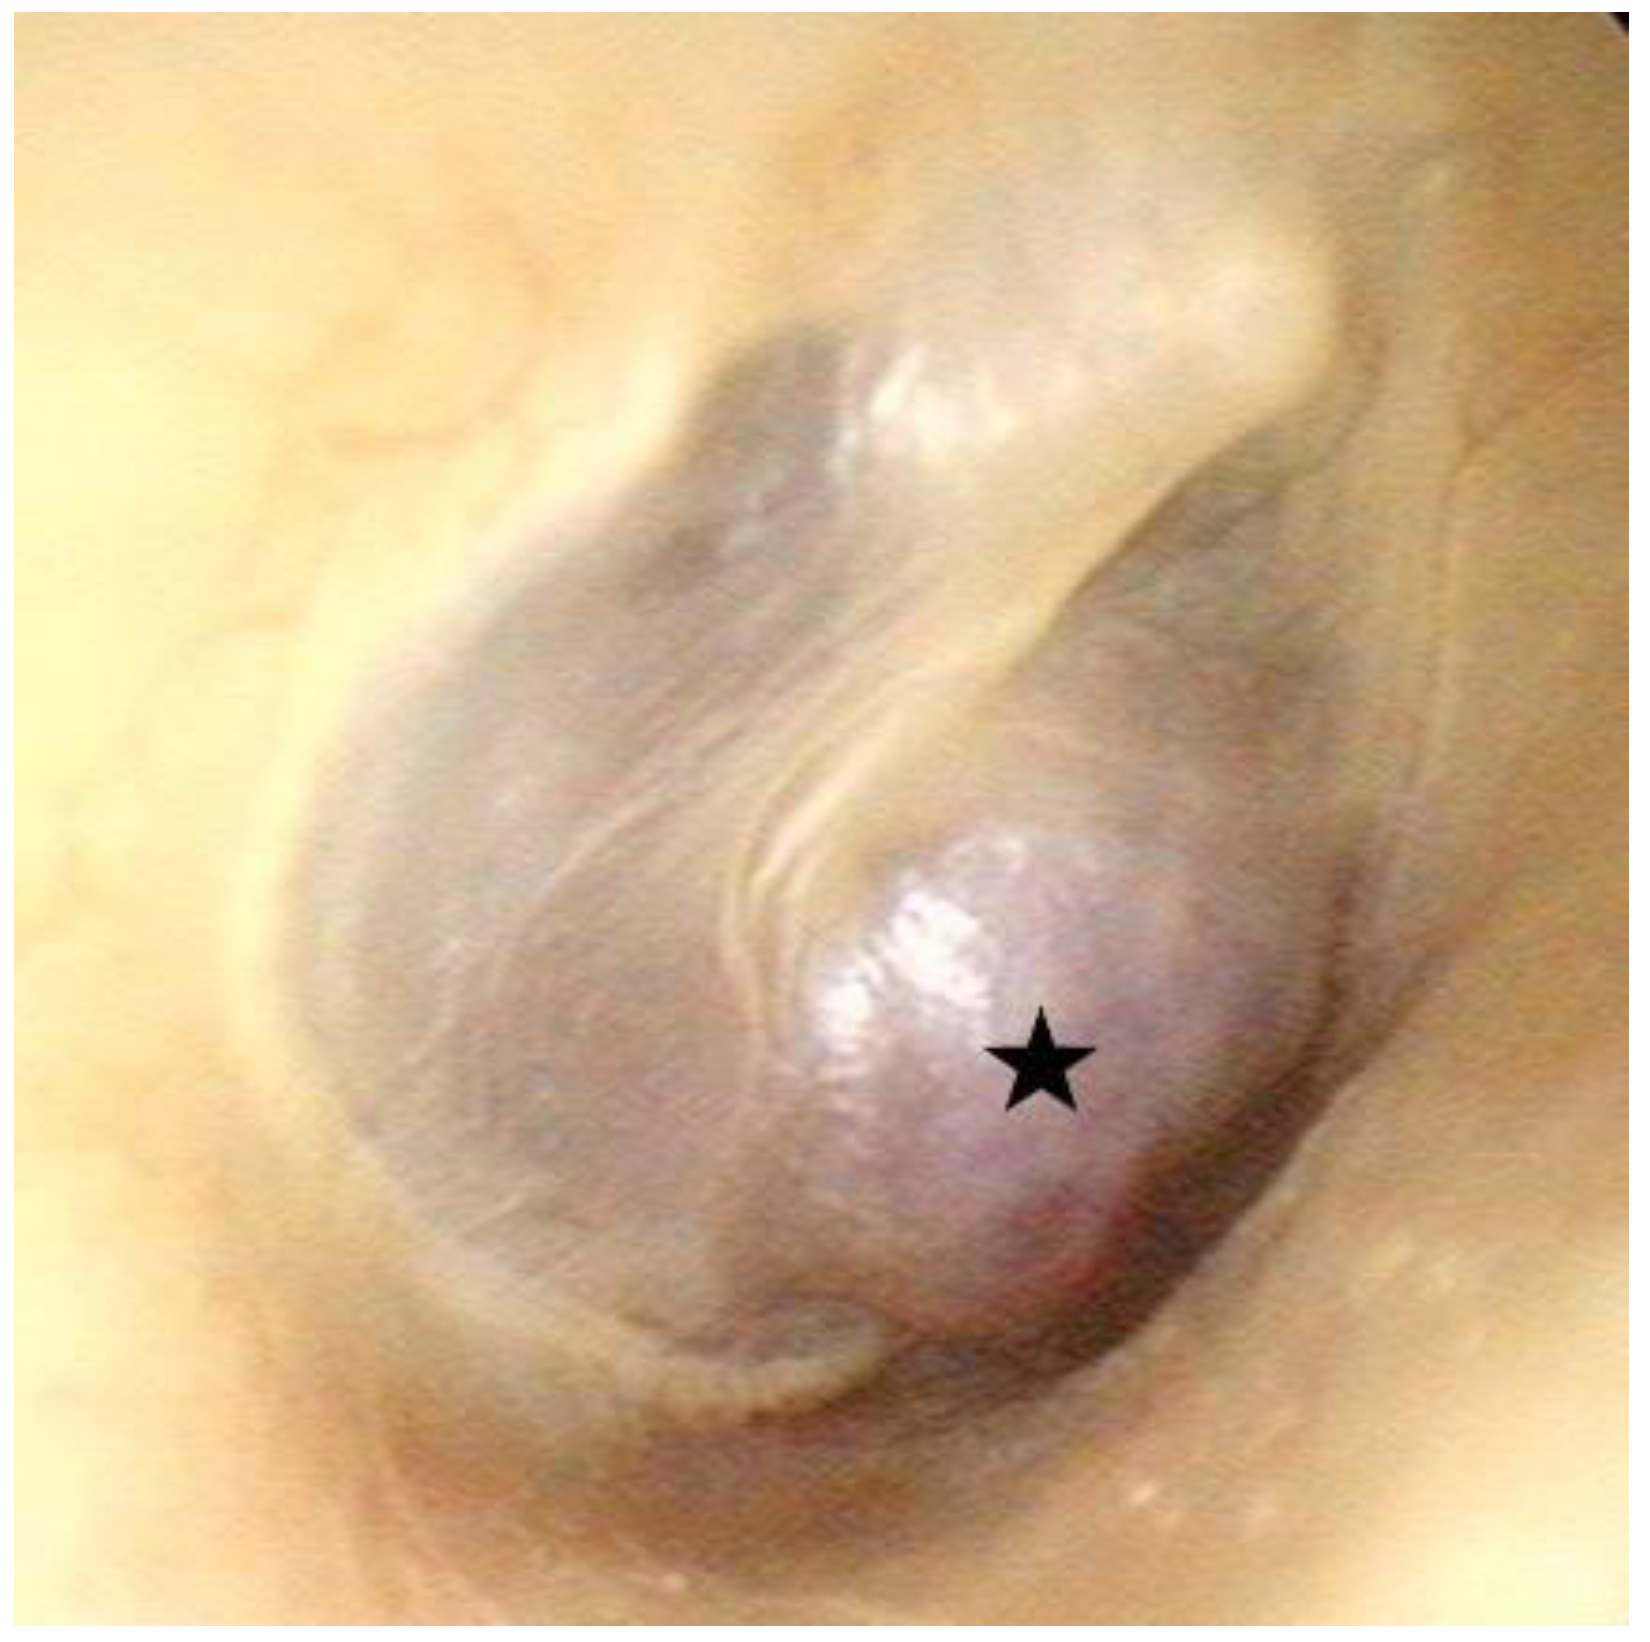

2. Case Report